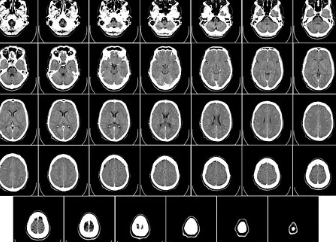

뇌경색 초기 증상에 대한 인지 및 대처 방법을 알고 있다면, 조기 진단 및 치료가 가능해지며 후유증을 예방할 수 있습니다. 뇌경색 초기증상을 인지하는 것은 매우 중요합니다. 뇌경색 초기증상이 있는 경우, 바로 응급실에 신고해야 합니다. 응급실에서는 CT 검사를 통해 뇌경색의 정확한 위치와 심각성을 파악할 수 있습니다.